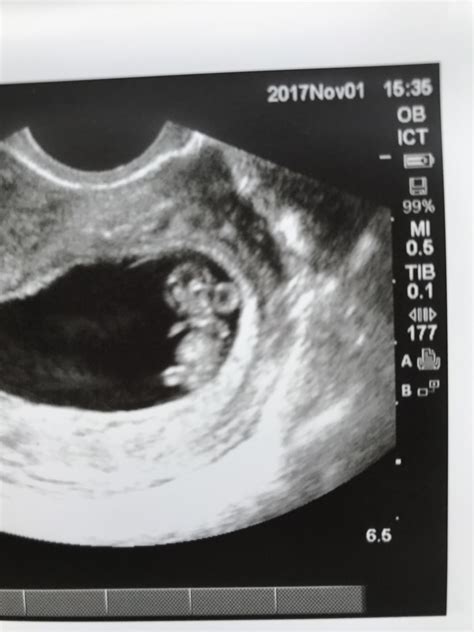

What Can Be Seen on an 8 Week Sonogram?

At 8 weeks, the fetus is still very small, but several key structures can be visualized:

• Gestational Sac: A fluid-filled structure that contains the developing embryo.

• Yolk Sac: A small, round structure that produces blood cells and helps in the early development of the embryo.

• Embryo: The developing fetus, which is about the size of a raspberry at this stage.

• Heartbeat: The fetal heartbeat is usually detectable and can be seen as a rapid flickering on the ultrasound screen.

• Neural Tube: The early stages of the brain and spinal cord can be observed.

Interpreting the Results of an 8 Week Sonogram

The results of an 8 week sonogram are interpreted by a trained ultrasound technician and reviewed by an obstetrician. Key findings include:

• Gestational Age: The CRL measurement helps determine the exact gestational age, which is crucial for monitoring the pregnancy’s progress.

• Fetal Heartbeat: The presence of a heartbeat is a positive sign of a viable pregnancy.

• Developmental Milestones: The ultrasound can confirm the presence of the yolk sac and the early stages of the neural tube.

• Potential Issues: Any abnormalities or complications, such as an ectopic pregnancy or signs of miscarriage, will be noted.